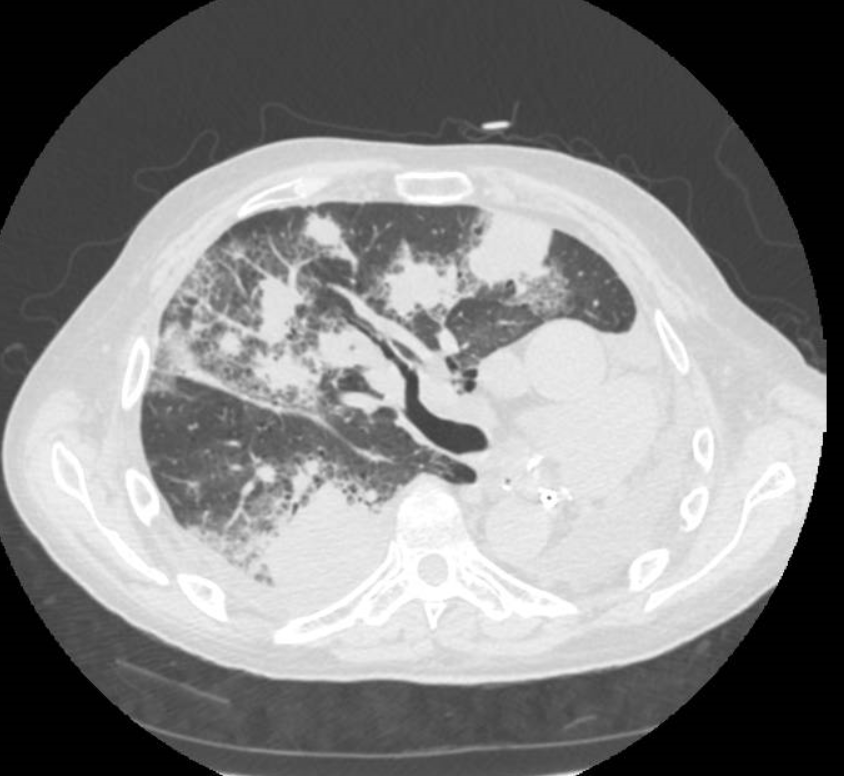

Varón de 35 años , fumador , consulta por tos y disnea de esfuerzo de 5 meses de evolución

dia 15 Empeoramiento clínico . Disnea. No fiebre